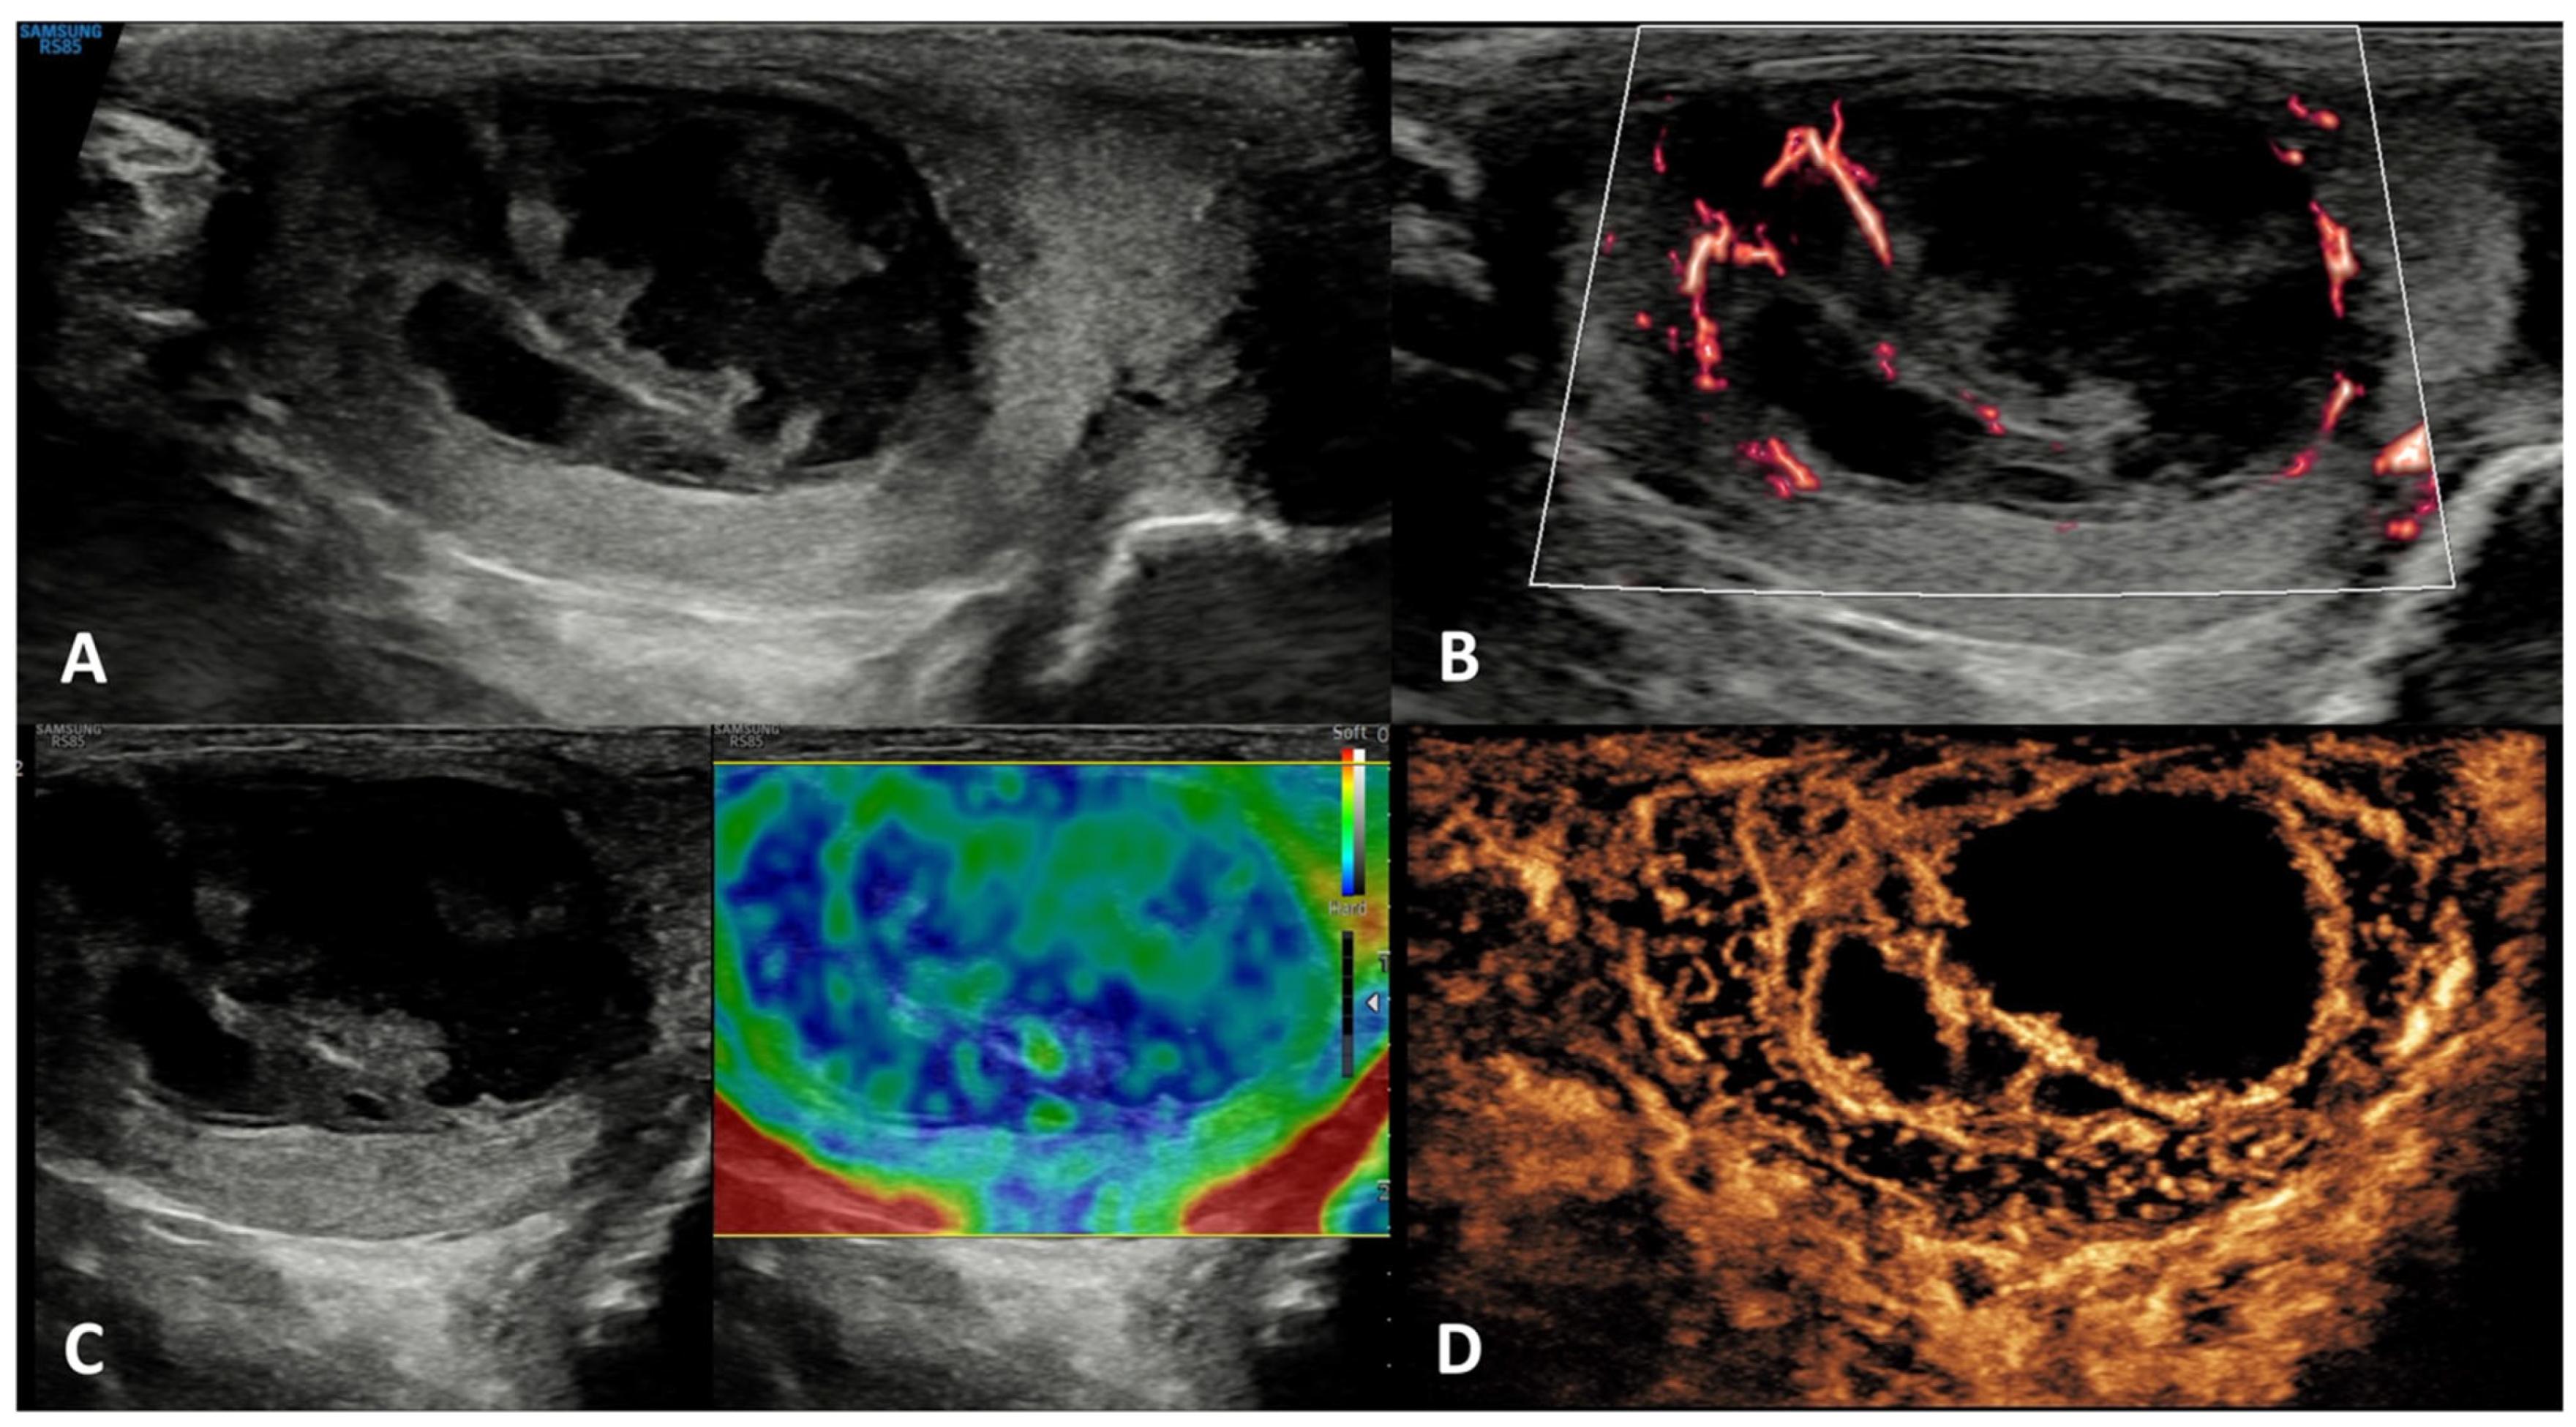

5.1. Seminomatous TGCTs (s-TGCTs)

| Seminoma | Testicular swelling, pain, lumbar pain OR asymptomatic palpable firm testicular mass; possible gynecomastia | possible increase of β-hCG | Hypoechoic homogeneous round or oval lesion, occasionally multinodular or with polycyclic lobulated margins (unfrequently inhomogeneous) | Hypervascularized, with arborization and branches | Homogeneously hyperenhanced (rapid wash-in and wash-out) | Hard lesions with low/absent elastic strain |